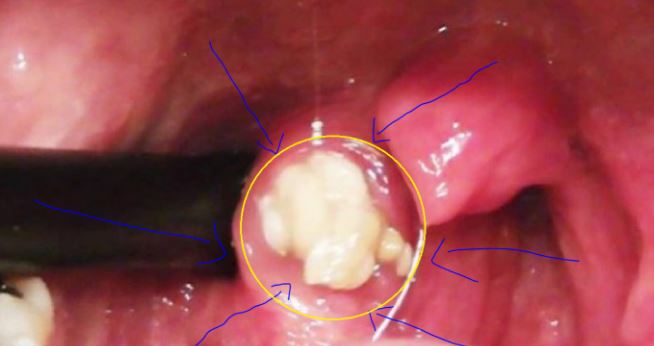

بالفيديو  :  اعتقدت أنها تملك شامة كبيرة.. لكن ما أخرجته الطبيبة كان صادماً!